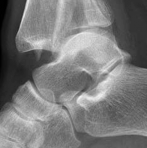

Temporary ankle-spanning external fixation was used to stabilize the fracture and soft tissues. X-rays taken after external fixation showed improved alignment and allowed for better understanding of the fracture pattern (Fig 2.2-2). Computed tomographic (CT) scanning with 3D reconstruction was performed for precise assessment of the fracture pattern of the tibial plafond. The CT revealed displaced fragments with a resultant intraarticular step-off and gap. The distal tibial metaphyseal fracture was multifragmentary. In addition, an associated long oblique fibular fracture was present (Fig 2.2-3).

Fig 2.2-3a–h A CT scan with 3D reconstruction.

a–d Sagittal (a–b), coronal (c), and axial (d) images demonstrate displaced posterior, anterolateral, and medial fracture fragments resulting in intraarticular step and gap. The incongruent tibiotalar joint is best appreciated on the sagittal scan.

e–h The 3D reconstructed images show the external fracture anatomy and general alignment.